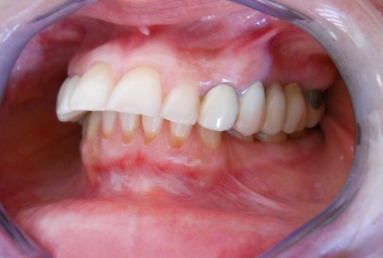

After treatment:

– zirconium/ceramic bridge in the lateral right maxillary area

– two implants and zirconium/ceramic bridge in the lateral left maxillary area

– full ceramic individual crowns in the frontal maxillary area, correcting at the same time the occlusion and the position of the frontal teeth.

– the lower arch was restored with a zirconium/ceramic bridge in the lateral right area and composite esthetic fillings + teeth whitening for the rest of the natural teeth.